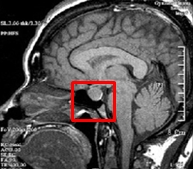

뇌하수체 기능부전(Hypopituitarism)

성장호르몬 결핍증(Growth hormone deficiency)

쿠싱 증후군(Cushing's syndrome)